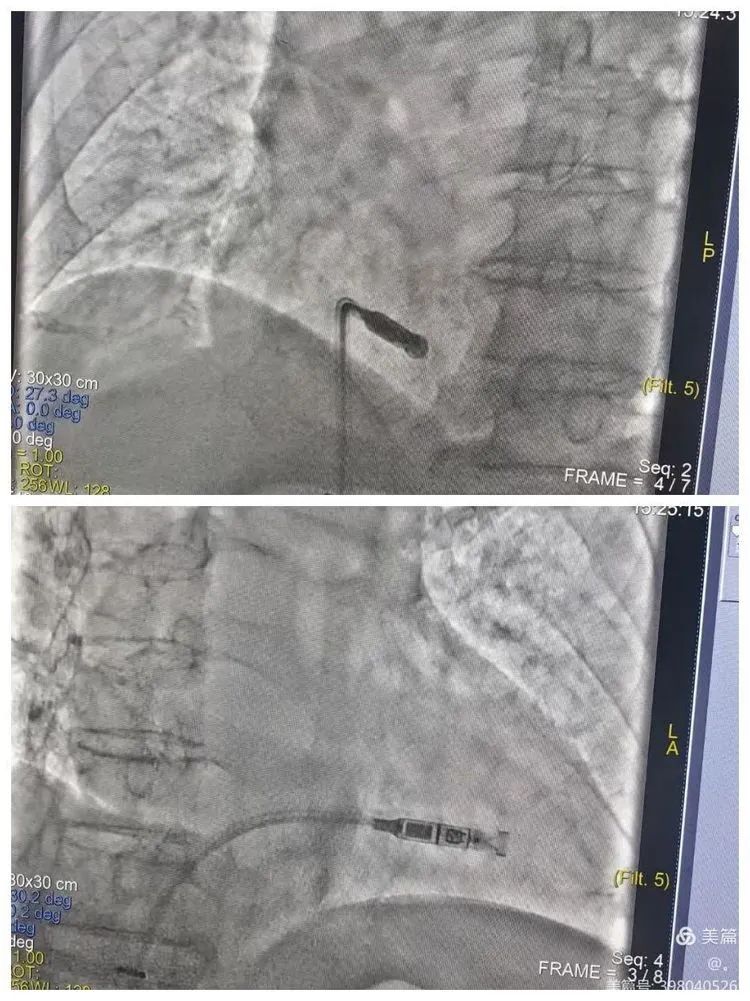

2024年5月6日心血管內(nèi)科心衰病區(qū)在劉志遠(yuǎn)主任團(tuán)隊(duì)的共同努力下,為一位八十八歲高齡的患者成功置入了Micra VR(無導(dǎo)線起搏器),為老人帶來了“心”的健康,同時(shí)也改善了病人的生活質(zhì)量。

無導(dǎo)線起搏器是集脈沖發(fā)生器與電極導(dǎo)線于一體的新型起搏器,無需靜脈植入心內(nèi)膜導(dǎo)線,而是以微縮膠囊的形式植入患者的心腔內(nèi),因此也無需皮下切口和囊袋。被媒體譽(yù)為“全球體積最小的心臟起搏器”。

1.微創(chuàng):無導(dǎo)線心臟起搏器的植入過程創(chuàng)傷小,可以通過股靜脈穿刺的方法植入患者體內(nèi),避免了傳統(tǒng)開胸手術(shù)的風(fēng)險(xiǎn)和痛苦。